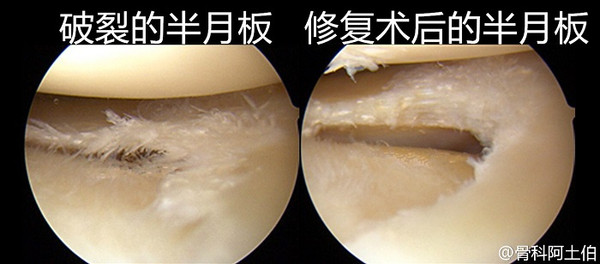

膝关节半月板损伤缝合修复术 医学百科

膝关节半月板损伤的关节镜微创手术

膝盖半月板损伤怎么办半月板是膝关节2个月牙形的纤维软骨,位于胫骨平台内侧和外侧的关节面。其横断面呈三角形,外厚内薄,主要起到传递负荷和弹性缓冲的作用。半月板破